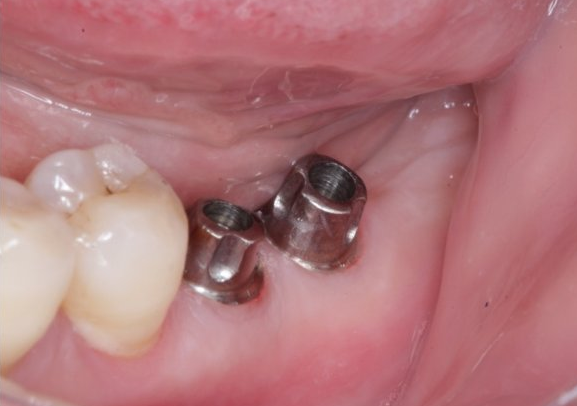

福州德尔齿科医生表示,一般来说,种植牙如果护理的好,使用寿命可达40年甚至终身,在发达国家,做了种植牙的人5年保存率在95%以上,10年保存率在90%左右。但种植牙的使用寿命其实与很多因素有关,以下为您做具体介绍:

越先进的种植牙系统,成功率越高,使用寿命也就越长。